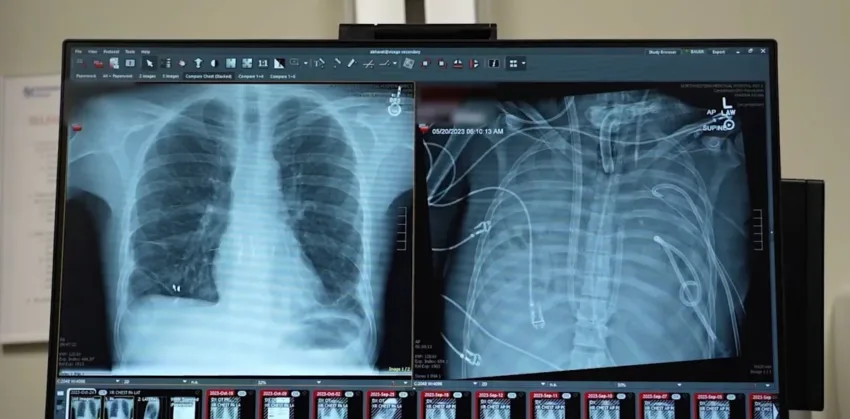

Un equipo de científicos ha conseguido que un paciente con una grave afección pulmonar sobreviva gracias a un sistema pulmonar extracorpóreo que le mantuvo vivo hasta que se le pudo realizar un doble trasplante de pulmón, una estrategia que podría emplearse como «puente salvavidas» hasta la intervención, según un estudio.

Para ello, el equipo diseñó un sistema extracorpóreo de pulmón artificial que sustituyó temporalmente las funciones pulmonares. El sistema oxigenaba la sangre, eliminaba el dióxido de carbono y ayudaba a mantener un flujo sanguíneo estable a través del corazón y el cuerpo.

Cuando se retiraron los pulmones infectados, la condición del paciente mejoró, su presión arterial se estabilizó, la función de los órganos se recuperó y la infección remitió.

Dos días después, llegaron los pulmones de un donante y los cirujanos realizaron un trasplante doble de pulmón. Más de dos años después, el paciente lleva una vida normal y tiene una buena función pulmonar.